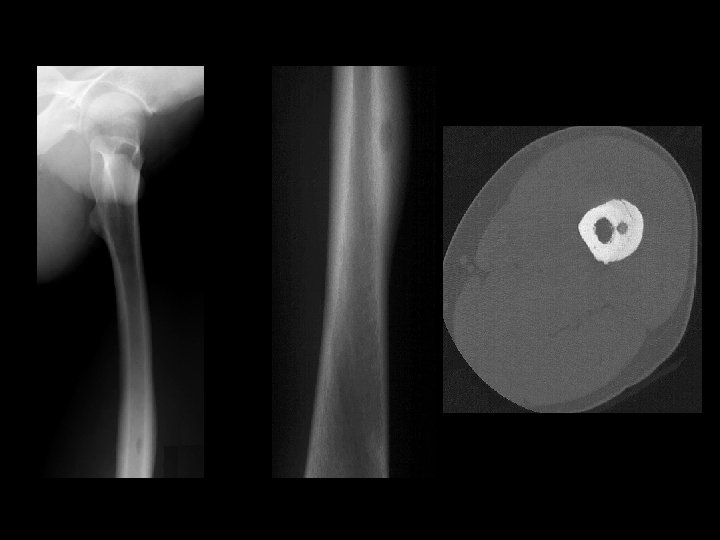

OSTEOID OSTEOMA • Small, benign, solitary painful lesion seen mainly in children & adolescents. • Any bone, tibia & femur…. . 50% Spine Painful Scoliosis

OSTEIOD OSTEOMA • Pain is the commonest presentation. • Pain is worsened by night, typically relieved by salicylates.

Example 8: 45 y/o with thigh pain

Example 8